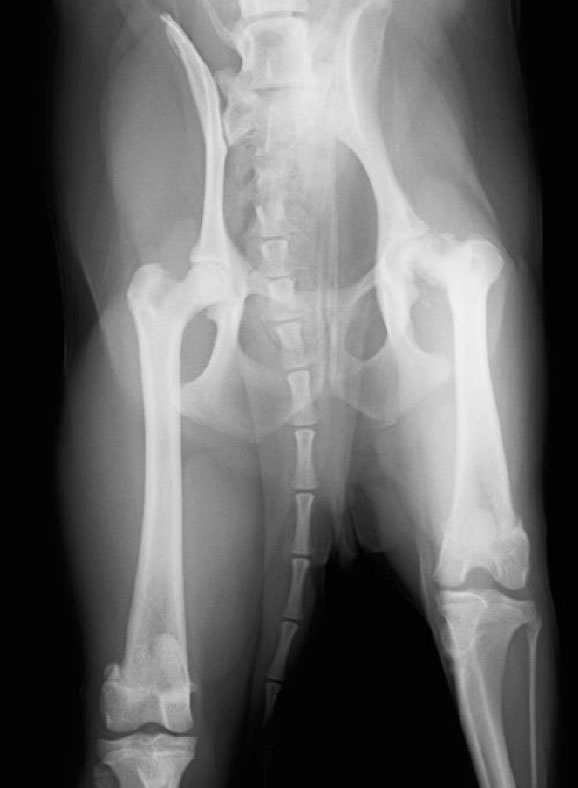

レッグペルテス 術前